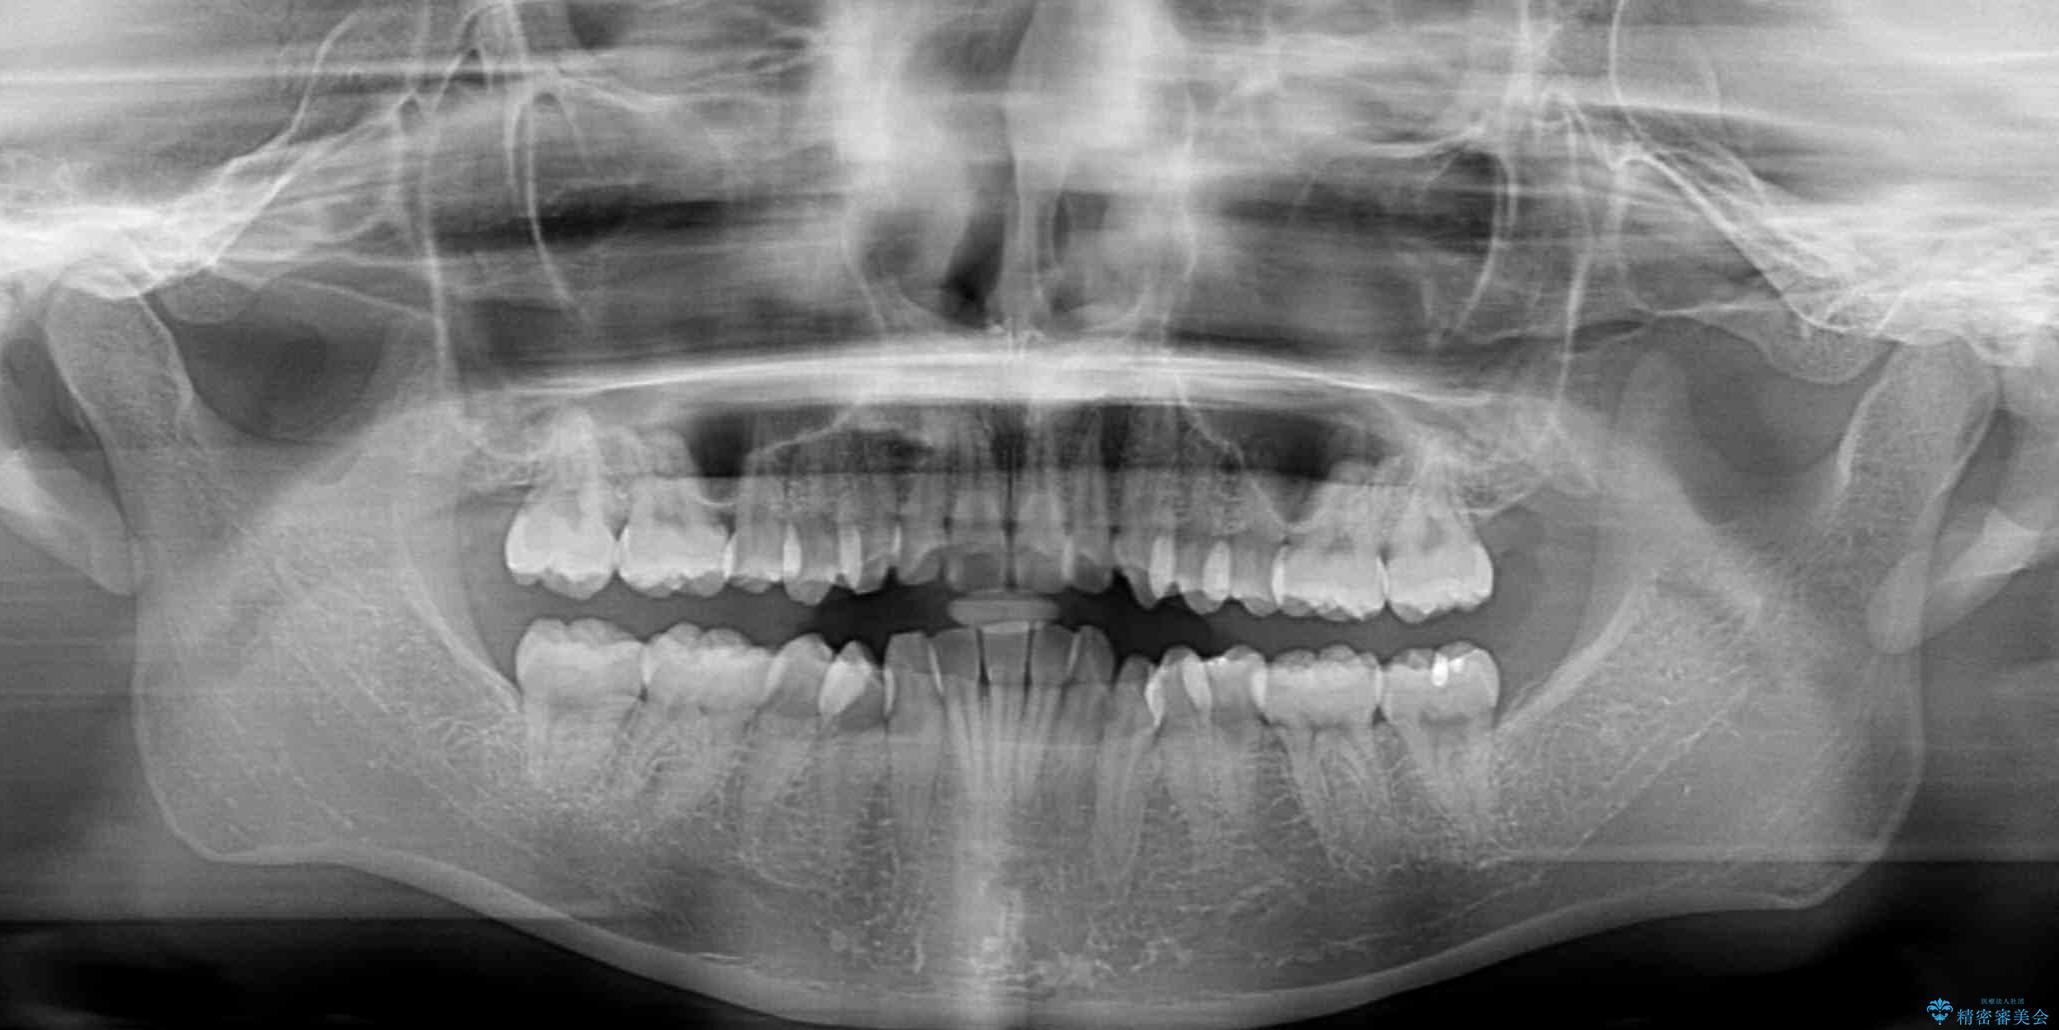

- 口を閉じたときに飛び出してしまう上顎前歯を気にして来院された患者様です。

下顎はデコボコが気になっていたため、上下左右第一小臼歯4本を抜去して、ワイヤー装置にて口元の突出感を改善するよう矯正治療を行うこととしました。

下唇に前歯が当たって跡が残ってしまう状態でしたが、スッキリとした口元に仕上げることができました。